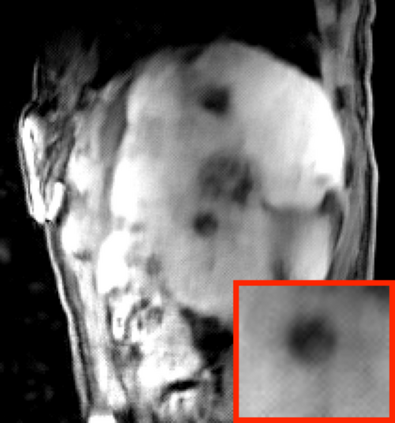

Deep neural networks for medical image reconstruction are traditionally trained using high-quality ground-truth images as training targets. Recent work onNoise2Noise (N2N) has shown the potential of using multiple noisy measurements of the same object as an alternative to having a ground truth. However, existing N2N-based methods cannot exploit information from various motion states, limiting their ability to learn on moving objects. This paper addresses this issue by proposing a novel motion-compensated deep image reconstruction (MoDIR) method that can use information from several unregistered and noisy measurements for training. MoDIR deals with object motion by including a deep registration module jointly trained with the deep reconstruction network without any ground-truth supervision. We validate MoDIR on both simulated and experimentally collected magnetic resonance imaging (MRI) data and show that it significantly improves imaging quality.